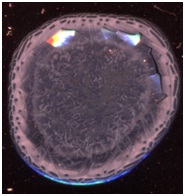

окрашенных тезиограмм плазмы крови больных гломерулонефритом были обнаружены

довольно разрозненные картины, не позволяющие выделить четкие морфотипы (рис1).

Рисунок 1.

Окрашенные амидочерным 10В тезиограммы плазмы крови больных гломерулонефритом.

Среди

окрашенных тезиограмм плазм крови больных гломерулонефритом можно было выделить

следующие общие признаки:

1)

Можно

выделить 3-4 концентрические зоны – краевая, центральная и промежуточная,

состоящая из двух подзон.

2)

Отсутствовали

радиальные трещины и центральная точка растрескивания.

3)

конкреции в центральной зоне фации.

4)

В

большинстве случаев в центральной зоне наблюдались кристаллические структуры

5)

Наблюдалось

незначительное увеличение краевой зоны.

6)

большинстве случаев в краевой зоне имелись конкреции, заполняющие всю площадь

сектора.